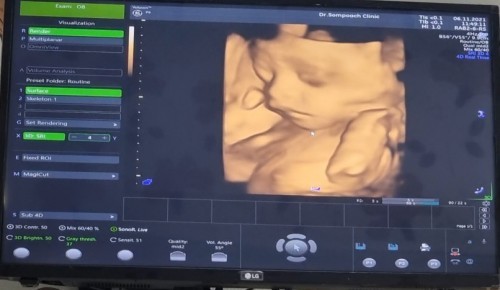

27wk แล้วครับ

เห็นหน้ากันสักทีนะ ก่อนหน้านี้มุดรกตลอด 😅😁